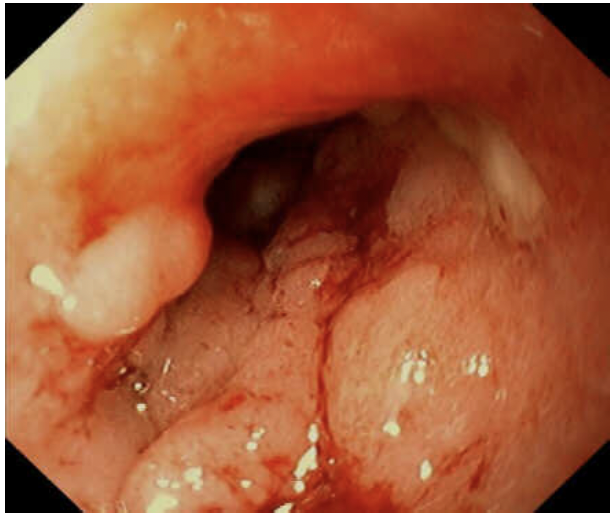

# MII Quelle est l'**anormalité** visualisée sur cette image endoscopique? Est-ce une colite ulcéreuse ou une maladie de Crohn? a) Muco-pus, colite ulcéreuse b) Muco-pus, maladie de Crohn c) Ulcérations linéaires, colite ulcéreuse d) Ulcérations linéaires, maladie de Crohn

a) Muco-pus, colite ulcéreuse